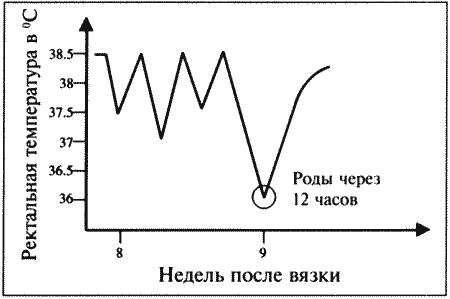

Роды

Снижение концентрации прогестерона перед родами наблюдается у большинства домашних животных и объясняется угнетением у беременной самки надпочечниковой секреции стероидных гормонов, что приводит к выработке эстрогена и простагландина эндометрием. У сук родам предшествует резкое падение концентрации прогестерона с 30 нмоль/л (10 нг/мл) до < 6 нмоль/л (< 2 нг/мл) в плазме крови; это, как сейчас принято считать, играет роль пускового механизма родов. Данный факт подтверждается и тем, что назначение прогестерона вызывает задержку родов, а препараты (например, эпостан), блокирующие его секрецию, — стимуляцию.

Резкое снижение концентрации прогестерона служит индикатором приближения родов. Концентрация > 6 нмоль/л (> 2 нг/мл) свидетельствует о том, что роды не начнутся в ближайшие 14 часов.